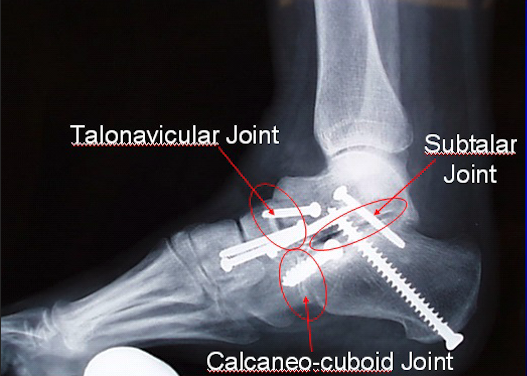

Triple arthrodesis is a surgical procedure used to treat severe hindfoot arthritis, deformity, or instability by fusing three joints of the hindfoot: the subtalar, talonavicular, and calcaneocuboid joints. These joints play a major role in side-to-side motion and foot adaptability.

Triple arthrodesis involves removing the remaining cartilage from the three hindfoot joints and positioning the foot in proper alignment. The joints are then stabilized with screws, plates, or other fixation devices to allow the bones to fuse into a single, stable construct.